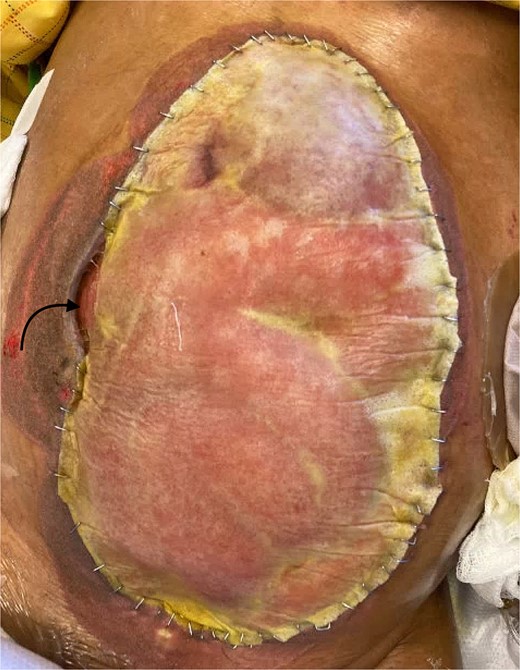

On hospital Day 11, after multiple reoperations the abdominal contents were notably frozen, and by hospital Day 18, a proximal small bowel EAF was appreciated (Fig. 1). On hospital Day 20, the patient developed hemorrhagic shock with bloody output from the nasogastric tube and hematochezia. Due to patient’s FA, decision was made to pursue endovascular intervention for suspected hepatobiliary arterial fistula. A supra-celiac arterial aortic occlusion balloon was placed in the intensive care unit, and visceral angiogram demonstrated frank hemorrhage into the bowel from the proper hepatic artery. Coil embolization from the left hepatic artery through the common hepatic artery was performed.

Frozen abdomen of the patient showing adhered loops of bowel and the lower lobe of the liver. The arrow represents the location where the patients fistula was located.